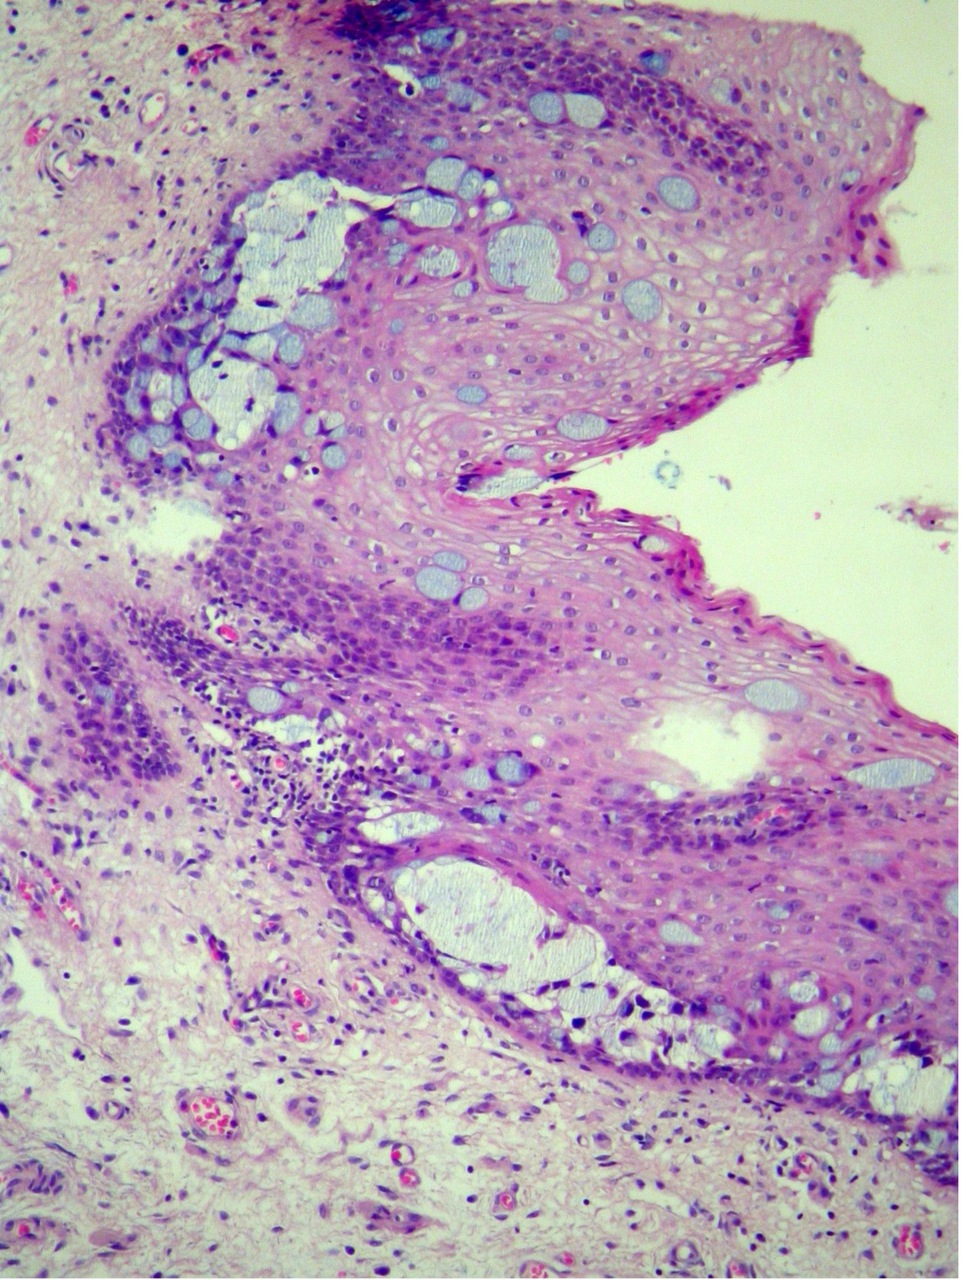

La maladie de Paget est un adénocarcinome intraépi­dermique. Elle peut être « primitive » lorsqu’elle est liée à l’extension épithéliale d’un adénocarcinome sous-cutané, ou « secondaire » à l’extension de contiguïté d’un cancer primitif anogénital ou viscéral synchrone distant, notamment colo­rectal, urologique, mammaire ou nasopharyngé.

L’analyse histologique permet le diagnostic (fig. 2). En outre, l’immunohistochimie oriente vers le type de cancer éventuellement associé.